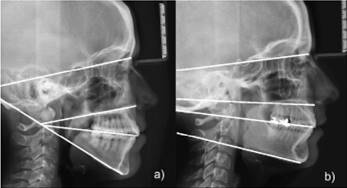

Dolicofacial: Posee mandíbulas con ramas poco desarrolladas en relación al cuerpo, cara alargada, arcadas dentarias angostas. Presentan divergencia entre la mandíbula y la base craneal y entre la base mandibular y el plano biespinal. Predominando el largo sobre el ancho en las dimensiones esqueletales. Su dirección de crecimiento es vertical (Fig 1a).

Braquifacial: Presentan mandíbulas con ramas potentes, caras anchas, arcadas dentarias bien desarrolladas, existe un mayor desarrollo muscular, dirección de crecimiento horizontal; éste se manifiesta por una rotación anterior de la sínfisis mandibular y el eje facial tiende a girar hacia adelante y arriba. El mentón es prominente y el surco mentolabial usualmente es marcado (Fig 1b).